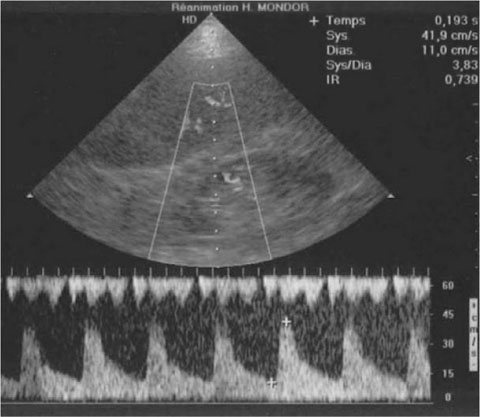

Fig. 1.

Example of an intrarenal arterial Doppler waveform

Renal sonography is performed routinely to assess renal and collecting system morphology. B-mode sonography provides valuable information on anatomic features including kidney size (longitudinal diameter and parenchyma thickness) and appearance (kidney margins and echogenicity of the parenchyma, cortex, medulla, and papillae); presence and degree of hydronephrosis; and presence of stones, calcification, cysts, or solid masses. However, B-mode sonography does not evaluate kidney function. Renal Doppler, in contrast, helps to assess renal perfusion and renal function of native or transplanted kidneys (Fig. 1). Renal Doppler is valuable for assessing large arterial or venous abnormalities and has been suggested for evaluating changes in intrarenal perfusion due to diseases of the renal parenchyma [1, 2, 3, 4, 5]. The Doppler-based renal resistive index is a recently suggested tool for assessing changes in renal perfusion in critically ill patients [6, 7, 8] and for predicting acute kidney injury (AKI) in patients with severe sepsis [9]. However, many factors influence the renal resistive index and should be taken into account when interpreting resistive index values in critically ill patients [10].